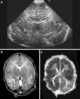

Cerebral shunts are commonly used to treat hydrocephalus, the swelling of the brain due to excess buildup of cerebrospinal fluid (CSF). If left unchecked, the cerebrospinal fluid can build up leading to an increase in intracranial pressure (ICP) which can lead to intracranial hematoma, cerebral edema, crushed brain tissue or herniation. [Source: Wikipedia ]